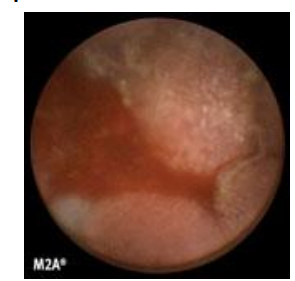

Capsule endoscopy

*not usually used in acute setting and clinical practice